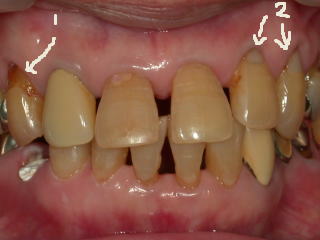

上の写真の2枚目の1が楔状欠損の大きいものです。詰めると2の様になります。

術前 下は2本詰めたのですが分かりますか? しみ止め塗布